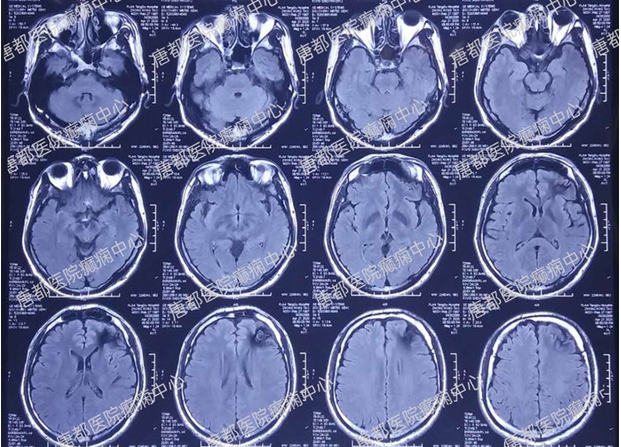

术前核磁检查:

左额叶海绵状血管瘤